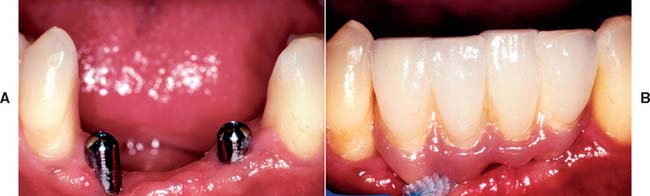

Today the continued high rate of success achieved with osseous integrated dental implants allows a greater number of patients to enjoy the benefits of fixed rather than removable dental prostheses.1-3 The main indications for implant-supported restorations in the partially edentulous patient are the free-end distal extension, in which no posterior abutment is available (Fig. 13-1), and the long edentulous span. In both these situations, the conventional dental treatment plan would include a partial removable dental prosthesis. However, with the advent of dental implants, the patient can benefit from fixed restorations. In addition, in the short edentulous span, the single dental implant is a popular option (Fig. 13-2).

Fig. 13-1 Implant-supported fixed prosthesis. Four dental implants (A) supporting a fixed dental prosthesis (B).